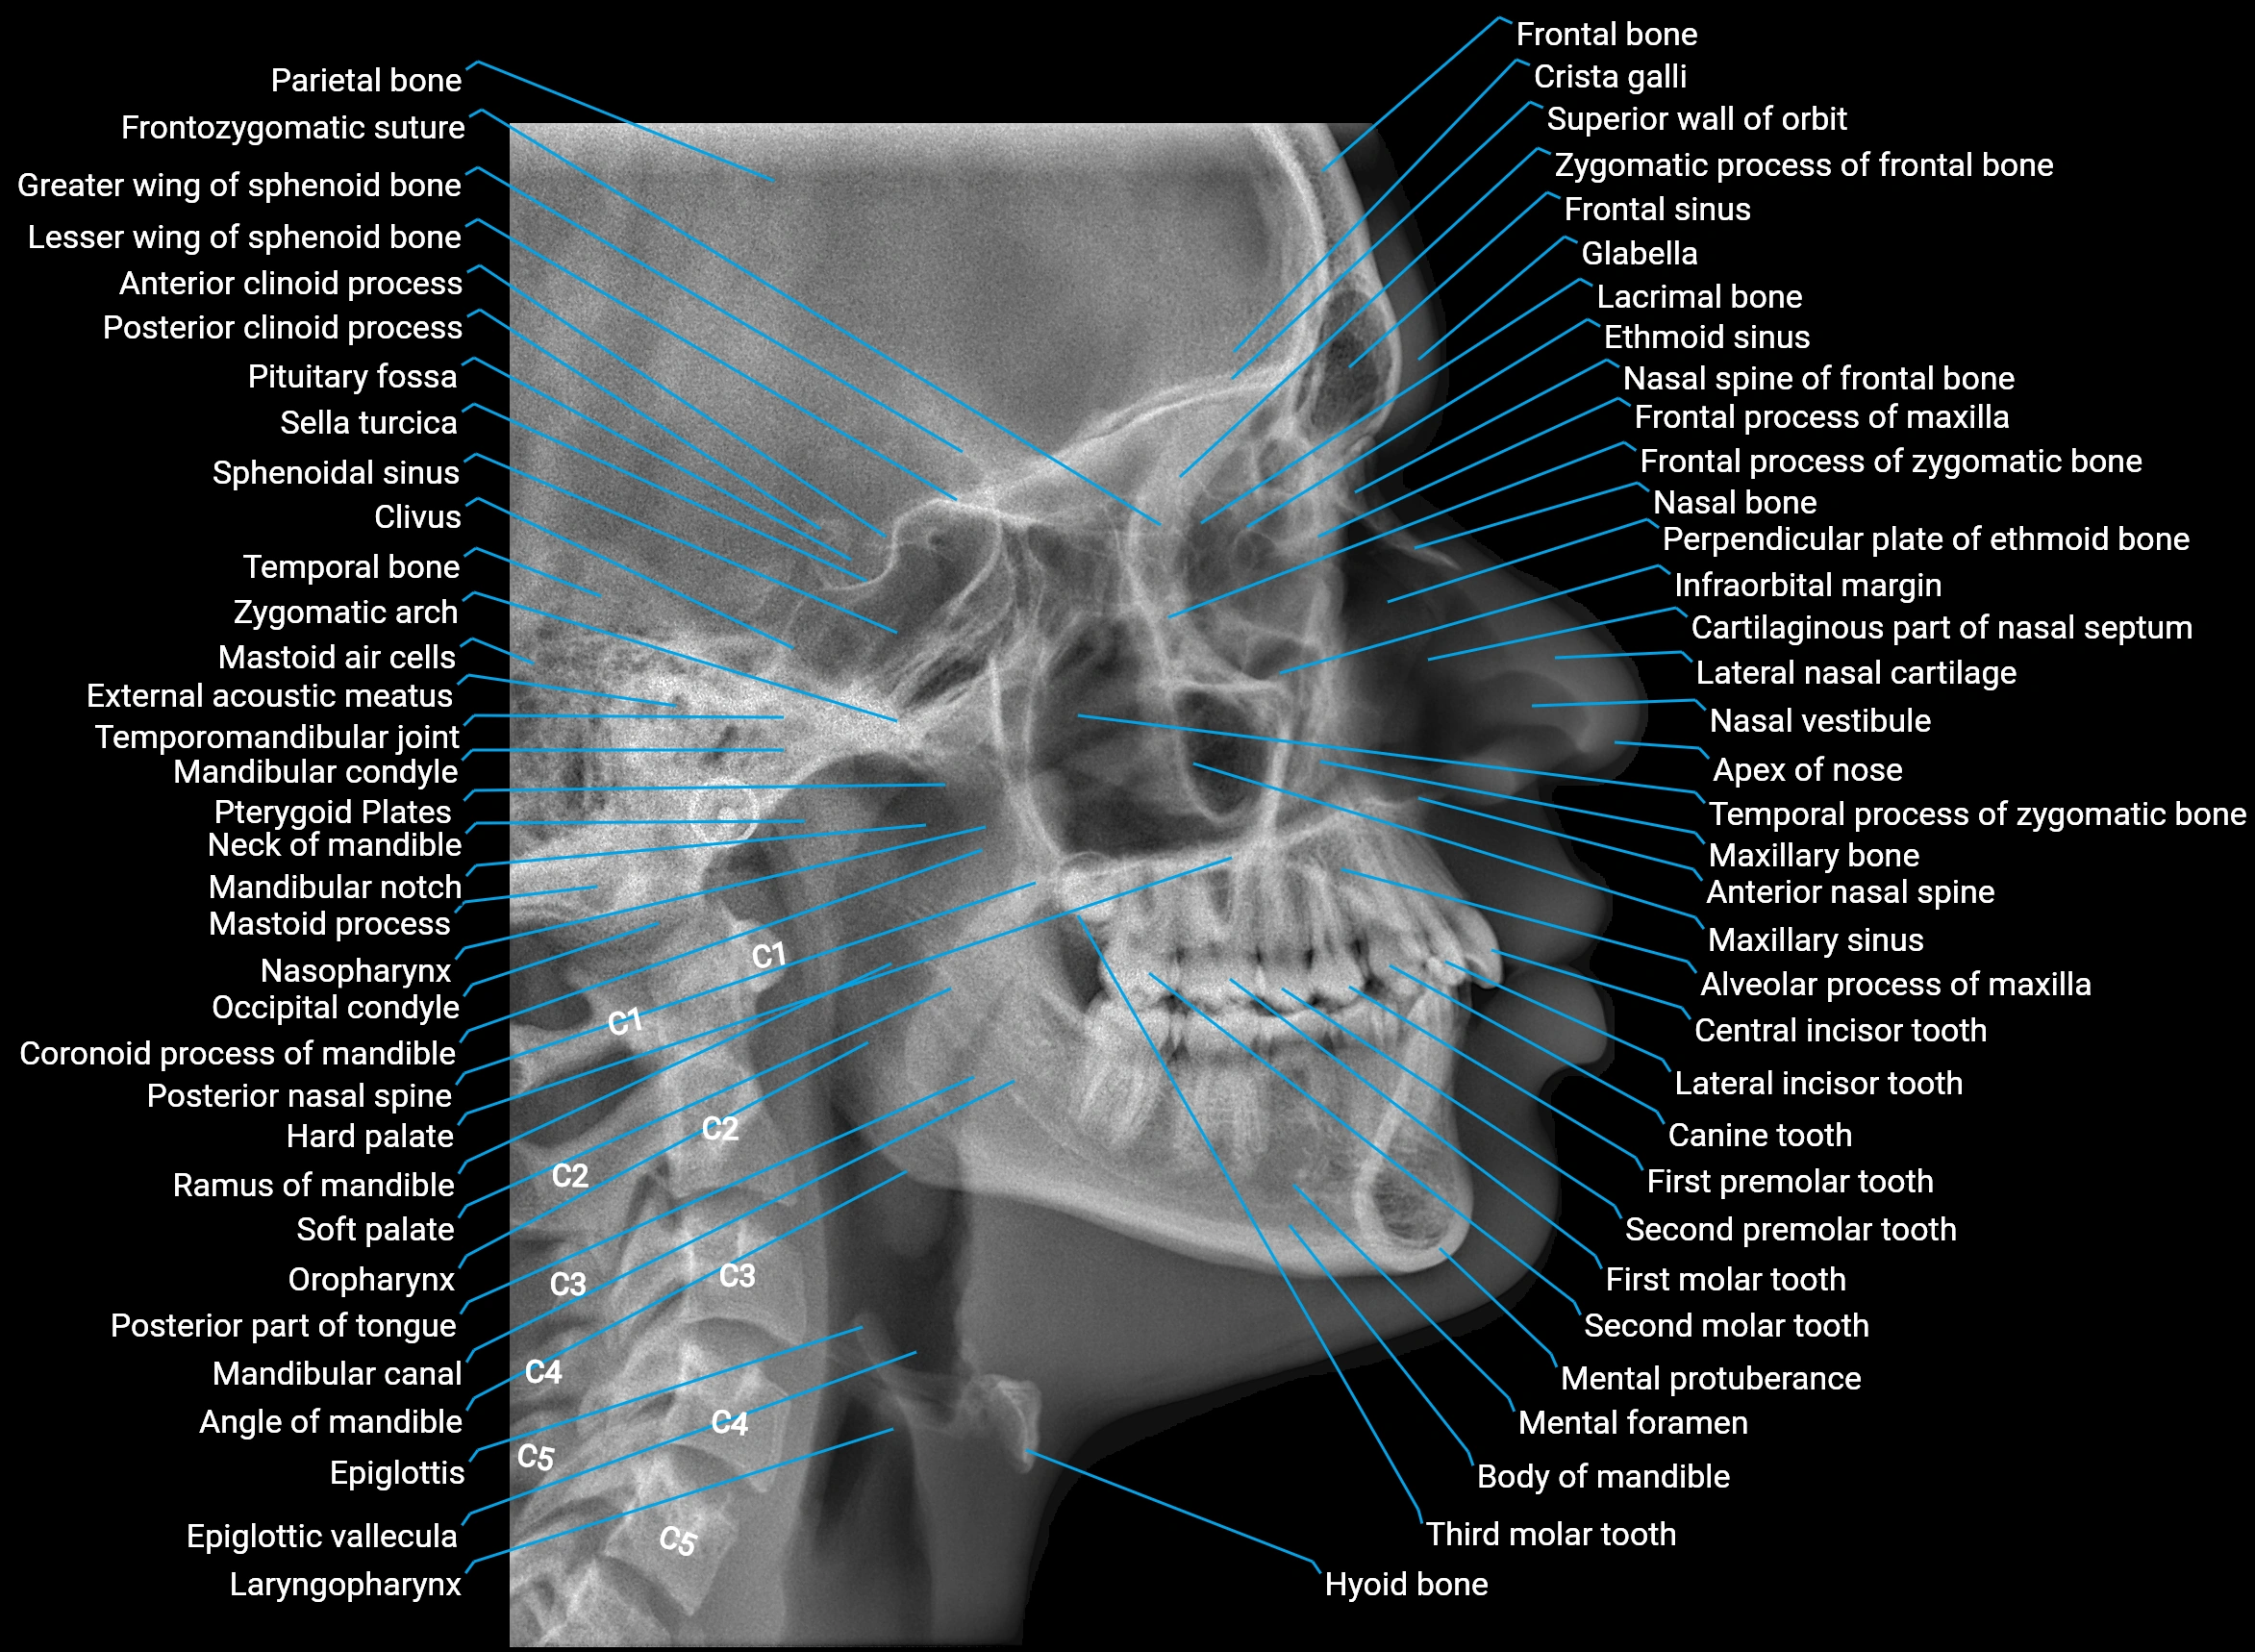

Alveolar process of maxilla

The alveolar process of the maxilla is the bony ridge of the maxilla that houses the upper teeth, extending from the anterior nasal spine to the maxillary tuberosity posteriorly. It consists of compact cortical bone on its outer surfaces and trabecular (cancellous) bone internally, with alveolar sockets (dental alveoli) forming individualized cavities for each tooth. The alveolar process develops in association with tooth eruption and resorption, adapting its shape and volume throughout life. It also forms part of the hard palate medially and contributes to the architecture of the midface, supporting the upper lip, cheeks, and nasal floor.